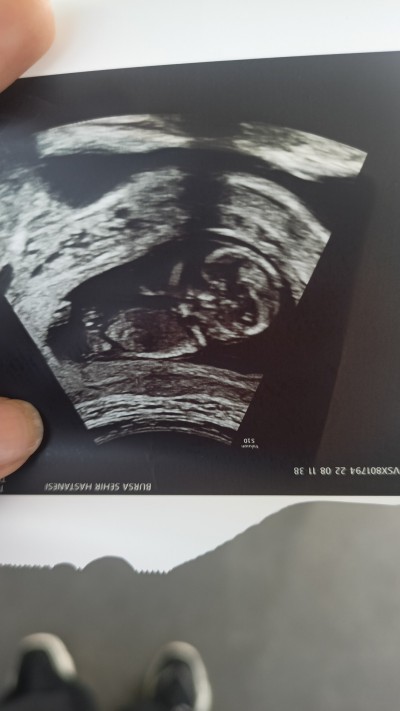

13+3 günlük hamileyim devlet hastanesi erken dedi söylemedi cinsiyetini tahmin etmek isteyen var mı acaba

Gebelik haftası 13+3